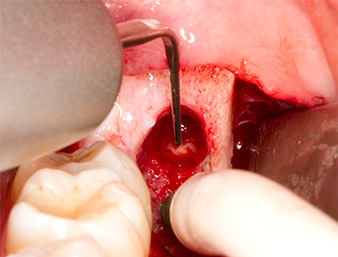

À l'aide d’un insert pour le débridement parodontal (Piezomed P1), l’espace ligamentaire parodontal de la racine résiduelle est ensuite élargi de manière minimale (Fig. 8).

Le même insert activé est inséré dans le canal radiculaire et détache le fragment sous l’effet de ses vibrations à micro-oscillations (Fig. 9, 10).